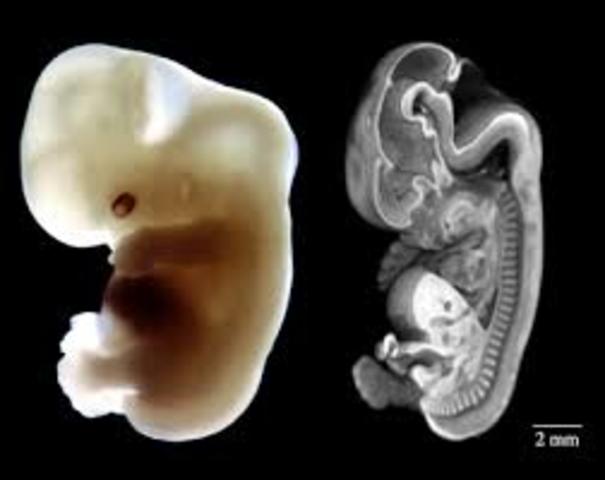

• embryonic stage

embryonic stage

the embryonic stage is where the fetus is becoming a baby and growing at a rapid speed. this goes until the fourth week until the eight week.

• body system

body system

This is where the fetus divides into three layers each will become an important body system. About 22 days after the conception the neural tube forms. this tube will later form into the central nervous system, the spinal cord and the brain. this domain is physical